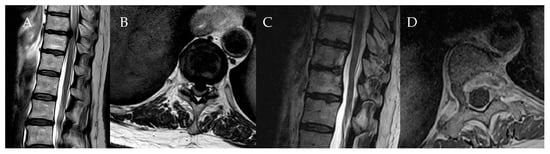

Surgical Treatment of Calcified Thoracic Herniated Disc Disease via the Transthoracic Approach with the Use of Intraoperative Computed Tomography (iCT) and Microscope-Based Augmented Reality (AR)

4. Patients

5.1. Surgical Technique and Outcome for Resection of Calcified Thoracic Disc

5.2. Anterolateral vs. Posterior Approach and Analysis of Clinical Outcomes